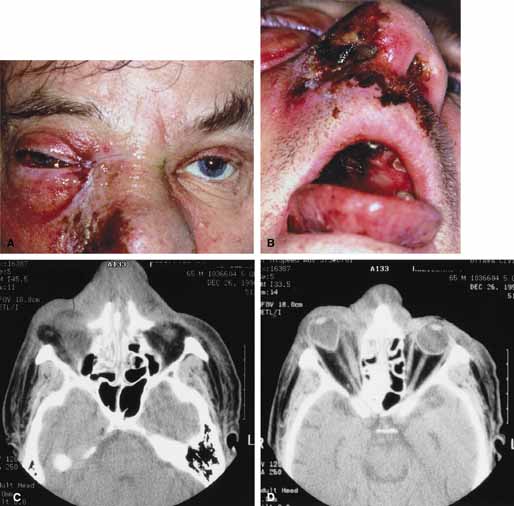

Although there have been a few reports of mucormycosis occurring in healthy individuals, virtually all other patients have had previous severe underlying disease. The patient most vulnerable to this infection is an one with uncontrolled diabetes with ketoacidosis. A host of other conditions also predispose patients to the disease including: multiple myeloma, lymphoma, organ transplantation with immunosuppresion, chemotherapy, corticosteroid treatment, acquired immunodeficiency syndrome, etc.(Fig. 2A).12–14 Mortality is extremely high for patients with phycomycosis infection, and successful treatment is contingent on early recognition and prompt treatment.

Fig. 2 A. A 65-year-old man with a myelodysplastic disorder and pancytopenia developed a pimple on the side of his nose followed by rapidly developing cellulitis and skin necrosis. The patient developed a frozen globe and loss of vision over a matter hours. Despite aggressive surgical debridement of the necrotic areas and intravenous, amphotericin, the patient died. B. Black eschar (necrosis) along right side of nose, ala, upper lip, and hard palate. C. Right orbital infiltration is seen along with opacification of the right ethmoid sinus and nasal passage. D. The optic nerve is on stretch with tethering of the globe, extensive soft tissue swelling anteriorly, ethmoidal opacification, and enlargement of the right medial rectus muscle.

Characteristic features of orbital mucormycosis include an immunocompromised patient with sinusitis, pharyngitis or nasal discharge who develops cellulitis of the face or lid. Signs and symptoms include orbital/periorbital pain, acute proptosis, abrupt visual loss, orbital apex syndrome with acute motility changes (external ophthalmoplegia), pupillary changes (internal ophthalmoplegia), ptosis, and decreased corneal sensation. Infarction of tissue results in black eschar formation of the skin, nasal mucosa and hard palate (Fig. 2A and 2B).12,13 With intracranial extension, the patient generally become obtunded, develops convulsions, contralateral hemianaesthesia or hemiplegia, and lapses into coma.

CT scanning demonstrates an orbital mass often with bone destruction and sinus involvement (Fig. 2C and 2D). The diagnosis is confirmed by biopsy of involved tissue with demonstration of characteristic nonseptate, large, branching hyphae, which can be seen on routine hematoxylin and eosin stains. Material should be submitted for both frozen and conventional paraffin-embedded sections. Frozen sections are not always definitive and the surgeon must have considerable confidence in the skill of the pathologist. 13 Management includes: (1) early definitive diagnosis; (2) correction of any underlying metabolic disturbance; (3) wide local excision with debridement of all involved and devitalized oral, nasal, sinus and orbital tissue; (4) establishment of adequate sinus and orbital drainage; (5) daily irrigation and packing of the involved orbital and paranasal areas with amphotericin B; and (6) intravenous amphotericin B.12,13,15